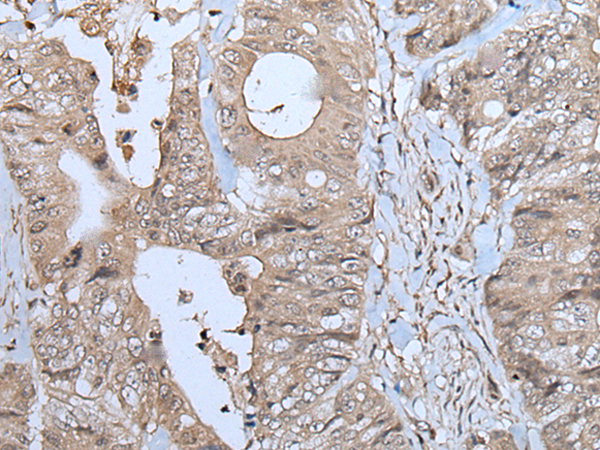

IHC positive control: |

Human colorectal cancer |

IHC Recommend dilution: |

25-100 |